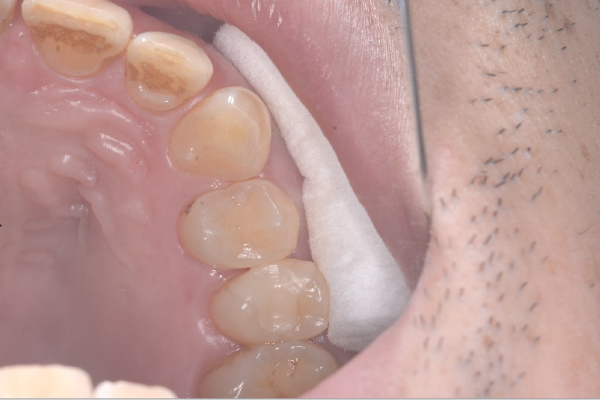

患者様の要望過去に治療したブリッジを外し咬み合わせの平面を整えて、被せ物や詰め物を綺麗にしたい。

治療期間10ヶ月

治療費用約1,600,000円

治療内容インプラント2本、アンカースクリューを用いた部分矯正、

セラミックによる補綴治療

治療のリスクセラミックの破折の

可能性